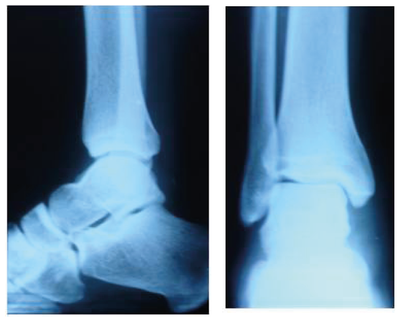

Uma paciente de 19 anos estava jogando handebol em uma competição da faculdade, quando, ao saltar para arremesso da bola, desequilibrou-se e “pisou em falso”. Queixa-se de muita dor no local. Ao exame físico local, nota-se edema (+2/4+), discreto hematoma e dor à palpação do maléolo lateral. Não consegue apoiar o pé no chão devido à dor. As duas imagens abaixo mostram duas incidências de radiografia simples do tornozelo da paciente. Considera-se a conduta mais apropriada para essa paciente o(a):

Answer

• encaminhamento para hospital ortopédico para possível conduta cirúrgica devido à fratura.

• encaminhamento para hospital ortopédico para possível conduta conservadora com uso de gesso devido à fratura.

• uso de gelo no local (até 3 vezes por dia por 30 minutos), anti-inflamatórios não esteroidais e uso de tala para imobilização analgésica por 5 a 7 dias.

• orientação de repouso relativo, uso de gelo no local (3 vezes por dia por 30 minutos) e de anti inflamatórios não esteroidais, liberando a paciente para ir para casa.